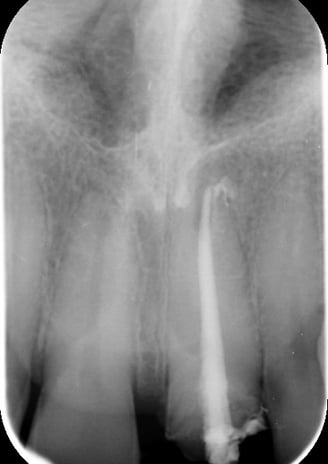

2. Sostituzione del Perno Moncone

Il perno moncone preesistente è stato rimosso e sostituito con un perno in fibra di vetro. Questo materiale offre vantaggi significativi:

Elasticità simile alla dentina naturale, riducendo il rischio di fratture radicolari.

Elevata adesione ai materiali compositi, garantendo una maggiore stabilità della ricostruzione.

Radiotrasparenza, permettendo un migliore controllo radiografico nel tempo.

3. Preparazione del Moncone e Impronte

Moncone ritentivo